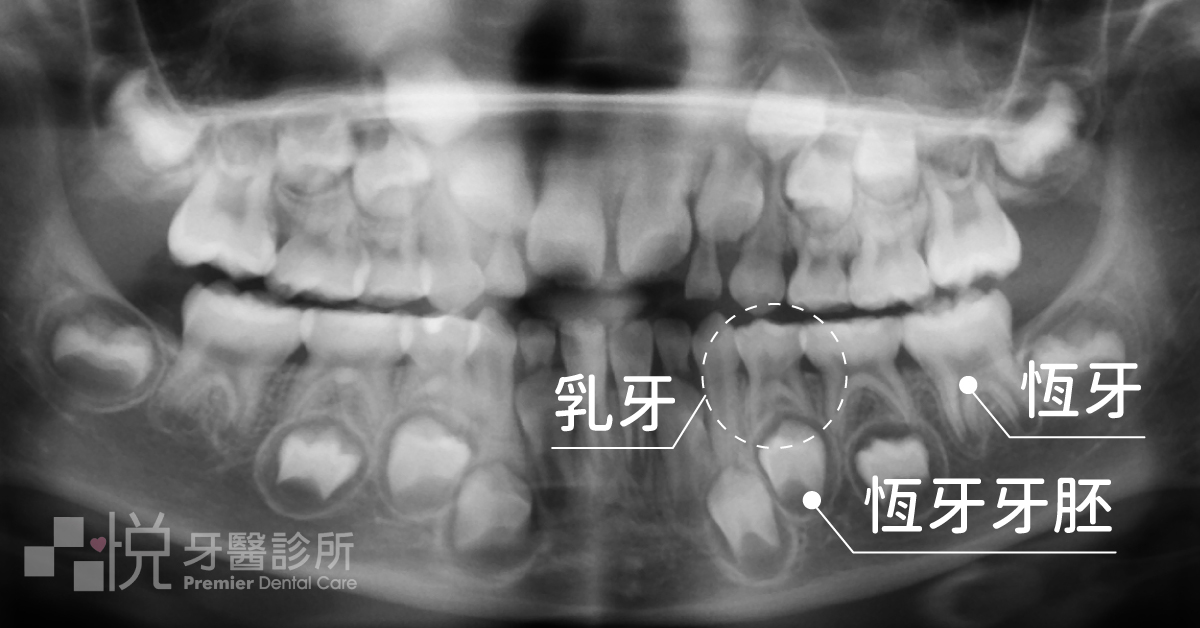

普遍來說,大家都知道換牙後「恆牙」的重要性,但有一部份人卻可能覺得「乳牙」不是很重要吧?不是會換牙嗎?有需要特別關注它嗎?

但其實乳牙在小朋友的生長階段有其存在的必要性,所以本篇文章就來讓大家認識一下,保護乳牙的好幫手 -「乳牙牙套」。

乳牙牙套是不會影響換牙的,他就像是一頂保護罩蓋在牙齒的頭和身體上,牙齒的腳在骨頭內並不受影響。

會影響換牙的是牙齒的腳(牙根)的健康程度,所以有時後被細菌感染過而做根管治療的乳牙會有提早或是延後脫落的狀況發生。

所以在換牙階段不需要特別再去拆除牙套,他是會隨著牙根的吸收,跟著乳牙本身一起脫落。